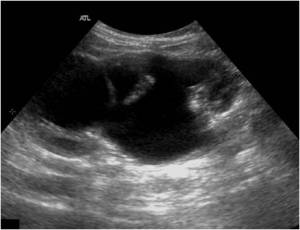

En la imagen 3 ves una imagen de un lipoma, mide 7 cms, la huella de la sonda mide 5cms, la «panoramic view» posee una regla centimetrada que sigue el contorno de la imagen, justo en la profundidad de la misma y lo marca la flecha amarilla. La profundidad la marca la flecha roja y la flecha blanca marca el rango centimetral de los 5cms, fíjate que la línea blanca es ligeramente mayor cada 5 cms. Sirve de referencia, como en la imagen 4 donde ves una colección en el glúteo de más de 10 cms.